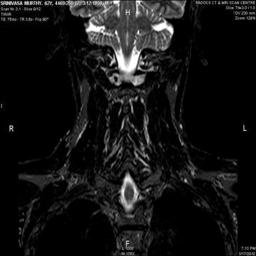

In order to show the proposed method in more detail, the algorithm is tested with other test images. The first row of Fig. 6 shows the original MRI image of thoracic spine with different views. The second row of Fig. 6 shows the same image enhanced using histogram equalization. Third row of Fig. 6 presents the MSR based enhancement scheme. Fourth row of Fig. 6 indicates Chao’s method of image enhancement. Finally, the reconstructed images using the proposed method is shown in fifth row of Fig. 6. Again, it can be seen from the results presented that the image enhancement using the proposed method is superior compared to other methods. This is evident from the image quality assessment presented in Table 1 using AWE and DWE.